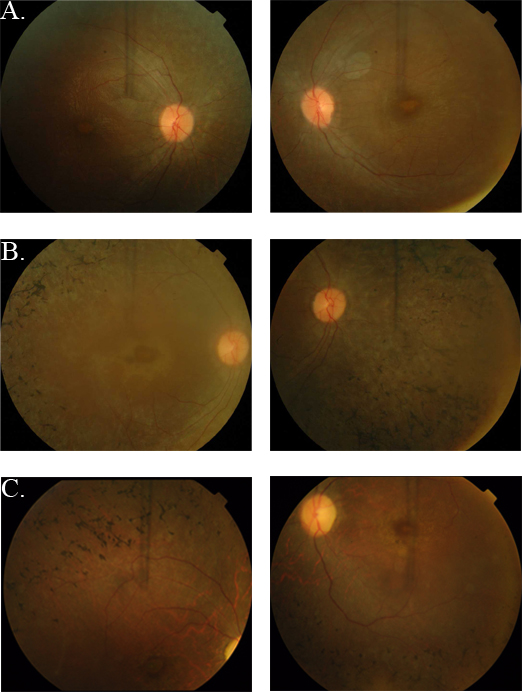

Figure 2. Fundus photographs of individuals with retinal dystrophy. A: OD and OS of individual 8 (affected, 25 years) of PKRP262. B: OD and OS of individual 12 (affected, 10 years) of PKRP262. C: OD and OS of individual 16 (affected, 12 years) of PKRP358. Fundus photographs of affected individuals show bone spicule-like

pigmentation in the mid-periphery of the retina, attenuated retinal arteriole, severe maculopathy, and disc pallor. OD = oculus

dexter; OS = oculus sinister.